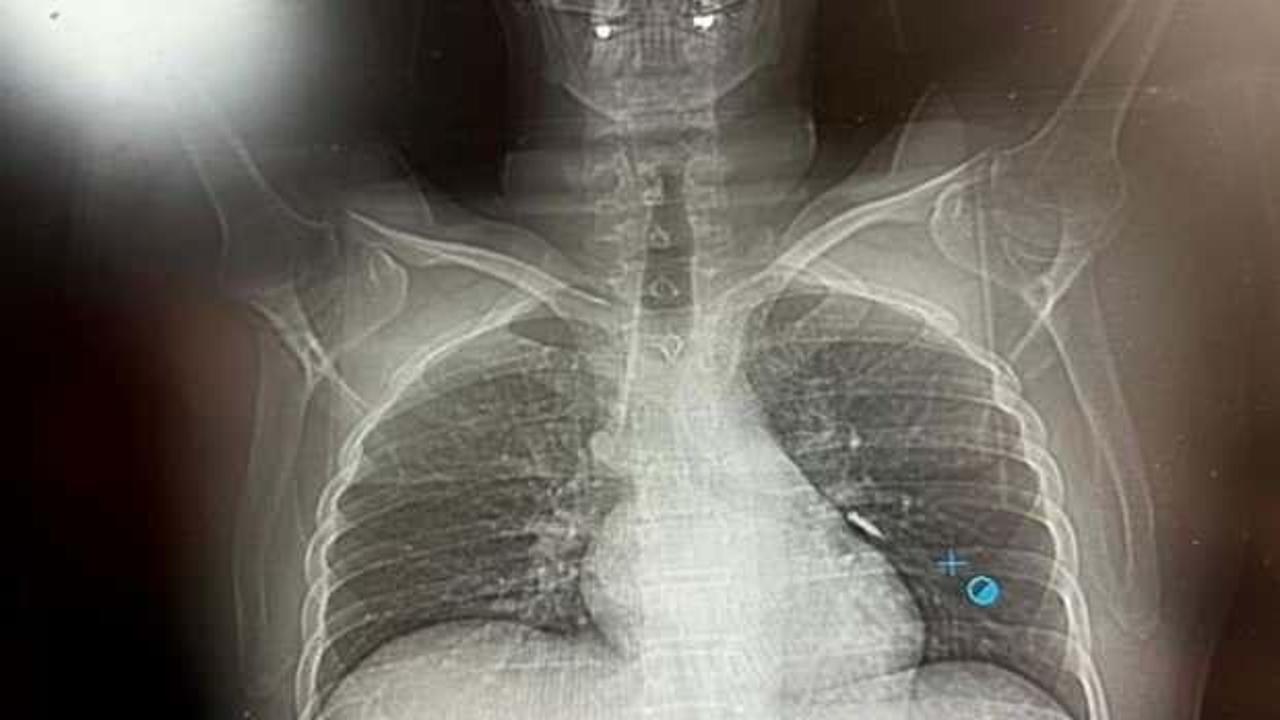

Van'ın İpekyolu ilçesinde ikamet eden F.T. isimli hasta, dış merkezli bir diş kliniğinde implant tedavisi gördüğü sırada, implant vidası yanlışlıkla soluk borusuna kaçtı.

Nefes borusuna kaçan vida nedeniyle hasta, ileri tetkik ve tedavi amacıyla Van Eğitim ve Araştırma Hastanesi'ne sevk edildi.

Hastaya bronkoskopi işlemi uygulandı. Sol akciğerin üst lobunda saplanmış şekilde tespit edilen vida, vidalı yapısı ve bulunduğu konum nedeniyle güçlükle yerinden oynatılabildi.

Yapılan uzun ve titiz müdahale sonrası vida yerinden çıkarılamasa da hasta bir süre sonra geçirdiği öksürükle birlikte implant vidasını midesine gönderdi. Vida, daha sonra doğal yollarla vücuttan atıldı.